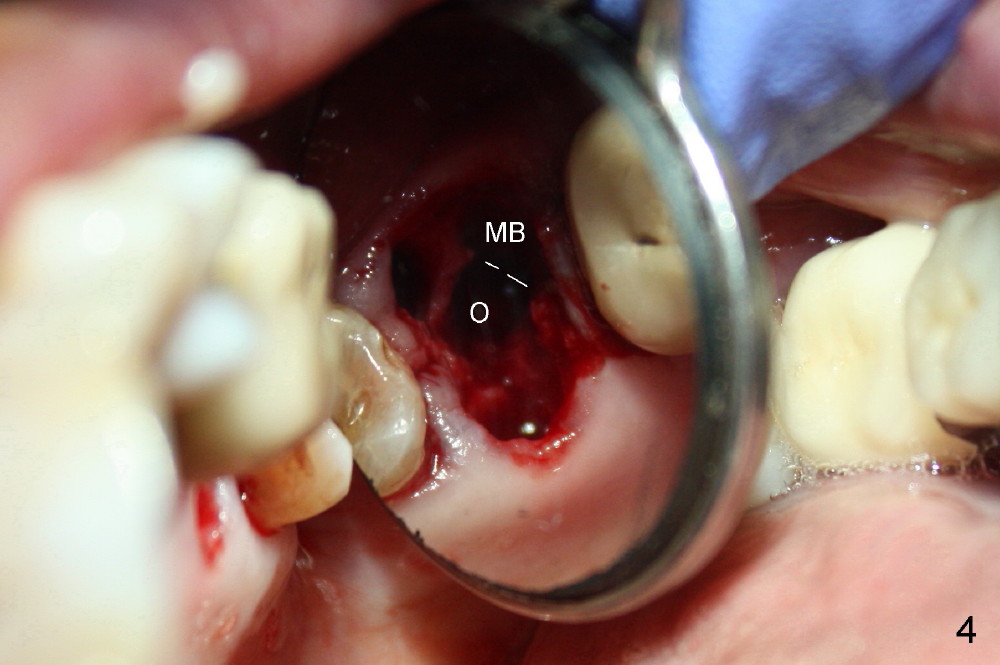

A 66-year-old lady requests restoring a broken tooth (Fig.1). Osteotomy is initiated in a thin septum (Fig.2 (occlusal mirror view) S) by sectioning, drilling and tapping (Fig.3 T). When 7x17 mm tap is removed, the osteotomy is found to form basically in the middle of socket (Fig.4 O). The apical portion of three sockets (Fig.5: MB, P and DB (not labeled) is packed with mixture of autogenous bone and allograft. When a 7x14 mm implant is placed, there are buccal and lingual gaps (Fig.6 *). The latter are bone grafted again (Fig.8 *) and require a coverage. After placement of a 4x3 mm abutment (Fig.7,8 A), an immediate provisional is fabricated (Fig.9 tissue surface view) to cover the remaining sockets (Fig.10 (occlusal mirror view), 11 (buccal view)). The provisional is infra-occlusal, i.e., load-free (Fig.11). The buccal and lingual aspects of the socket are covered by fresh epithelium 8 days postop (Fig.12 <). The implant appears to have osteointegrated 4 months postop (Fig.13). The tooth #16 appears to have shifted mesially. It is difficult to prepare for #15 crown. Luckily the patient agrees to have it extracted because of persistent sensitivity after MO composite. The definitive crown at the site of #15 is cemented 6 months postop (Fig.14).